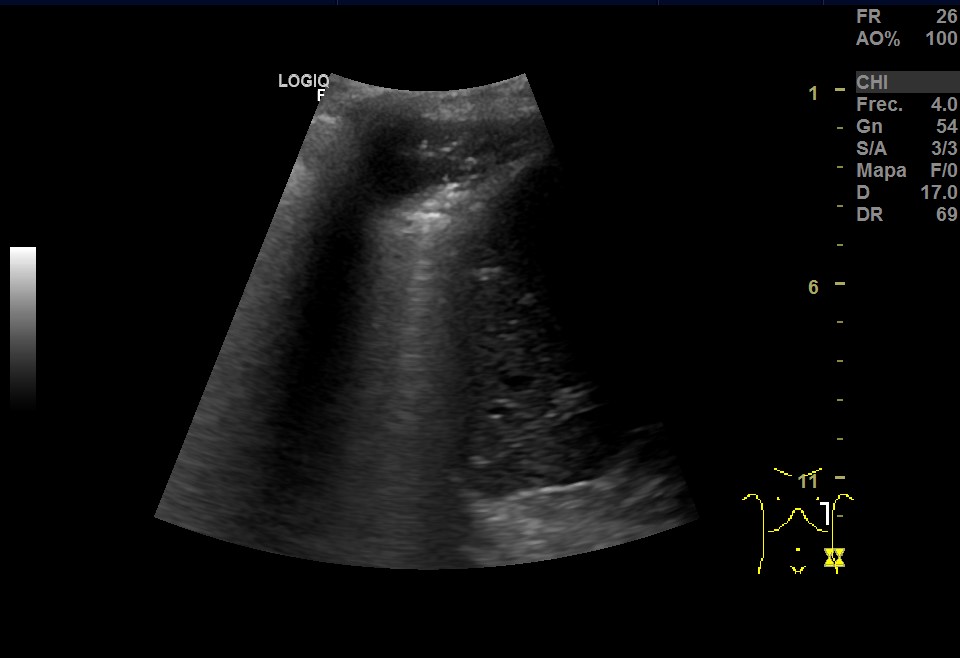

Ecografía pulmonar: imagen hipoecoica irregular subpleural, con signo de desflecamiento, limitada superiormente por la línea pleural e inferiormente por una línea irregular en sacabocados donde aparece un punteado hiperecoico sobre múltiples líneas B que muestran imagen de pulmón blanco. Todo ello sugestivo de consolidación pulmonar con broncograma aéreo. Imagen de medusa sugestiva de pequeño derrame pleural.